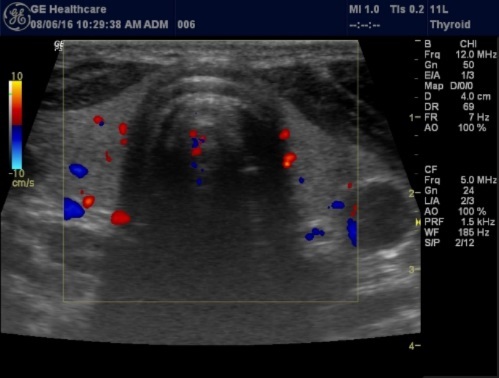

High-resolution ultrasonography (USG) is the most accurate and cost-effective method for evaluating and observing thyroid nodules 3. Although there is some overlap between ultrasound appearance of benign and malignant nodules, certain USG features are helpful in differentiating the two. Iso-or hyper-echogenicity of the thyroid nodule in conjunction with a spongiform appearance is the most reliable criterion for benignity of the nodule on gray-scale ultrasound, Figure 4A. Other features like nodule size <1 cm, width > length, presence of hypoechoic or hyperoechoic halo around the nodule, Figure 4A and Figure 4B, caused by fibrous capsule compressing thyroid tissue, and coarse/curvilinear calcification are less specific but may be useful ancillary signs4 ,6. "Ring down" or "comet-tail" artifact or sign is typical of benign cystic colloid nodule, Figure 520. Perinodular flow or spoke-and-wheel-like appearance of vessels on color Doppler examination is characteristic of a benign thyroid nodule. However, this flow pattern may also be seen in thyroid malignancy. A complete avascular nodule is very unlikely to be malignant 4.

Histologically, if the excised gland has volume <500 mm3 it is said to be hyperplastic and if the volume is more than 500 mm3 it is nodular hyperplasia in 80% of cases26. In secondary HPT, the increase in the volume of parathyroid glands is associated with increase in vascularity, as evident in Color Doppler imaging 27.